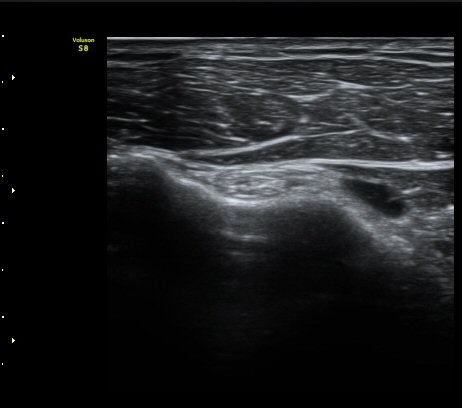

ÃÊÀ½ÆÄ °Ë»ç

À̵ιڱ٠Á¾´Ü¸é°Ë»ç»ó ƯÀÌ ¼Ò°ßÀ» º¸ÀÌÁö ¾ÊÀ¸³ª(±×¸² 1)  ŽÃËÀÚ¸¦ ¾Æ·¡·Î À̵¿ÇÏ´Ï

°ß°©ÇÏ±Ù°Ç ³»Ãø¿¡¼­ ¼ö¾×Àú·ù°¡ °üÂûµÈ´Ù(±×¸² 2).